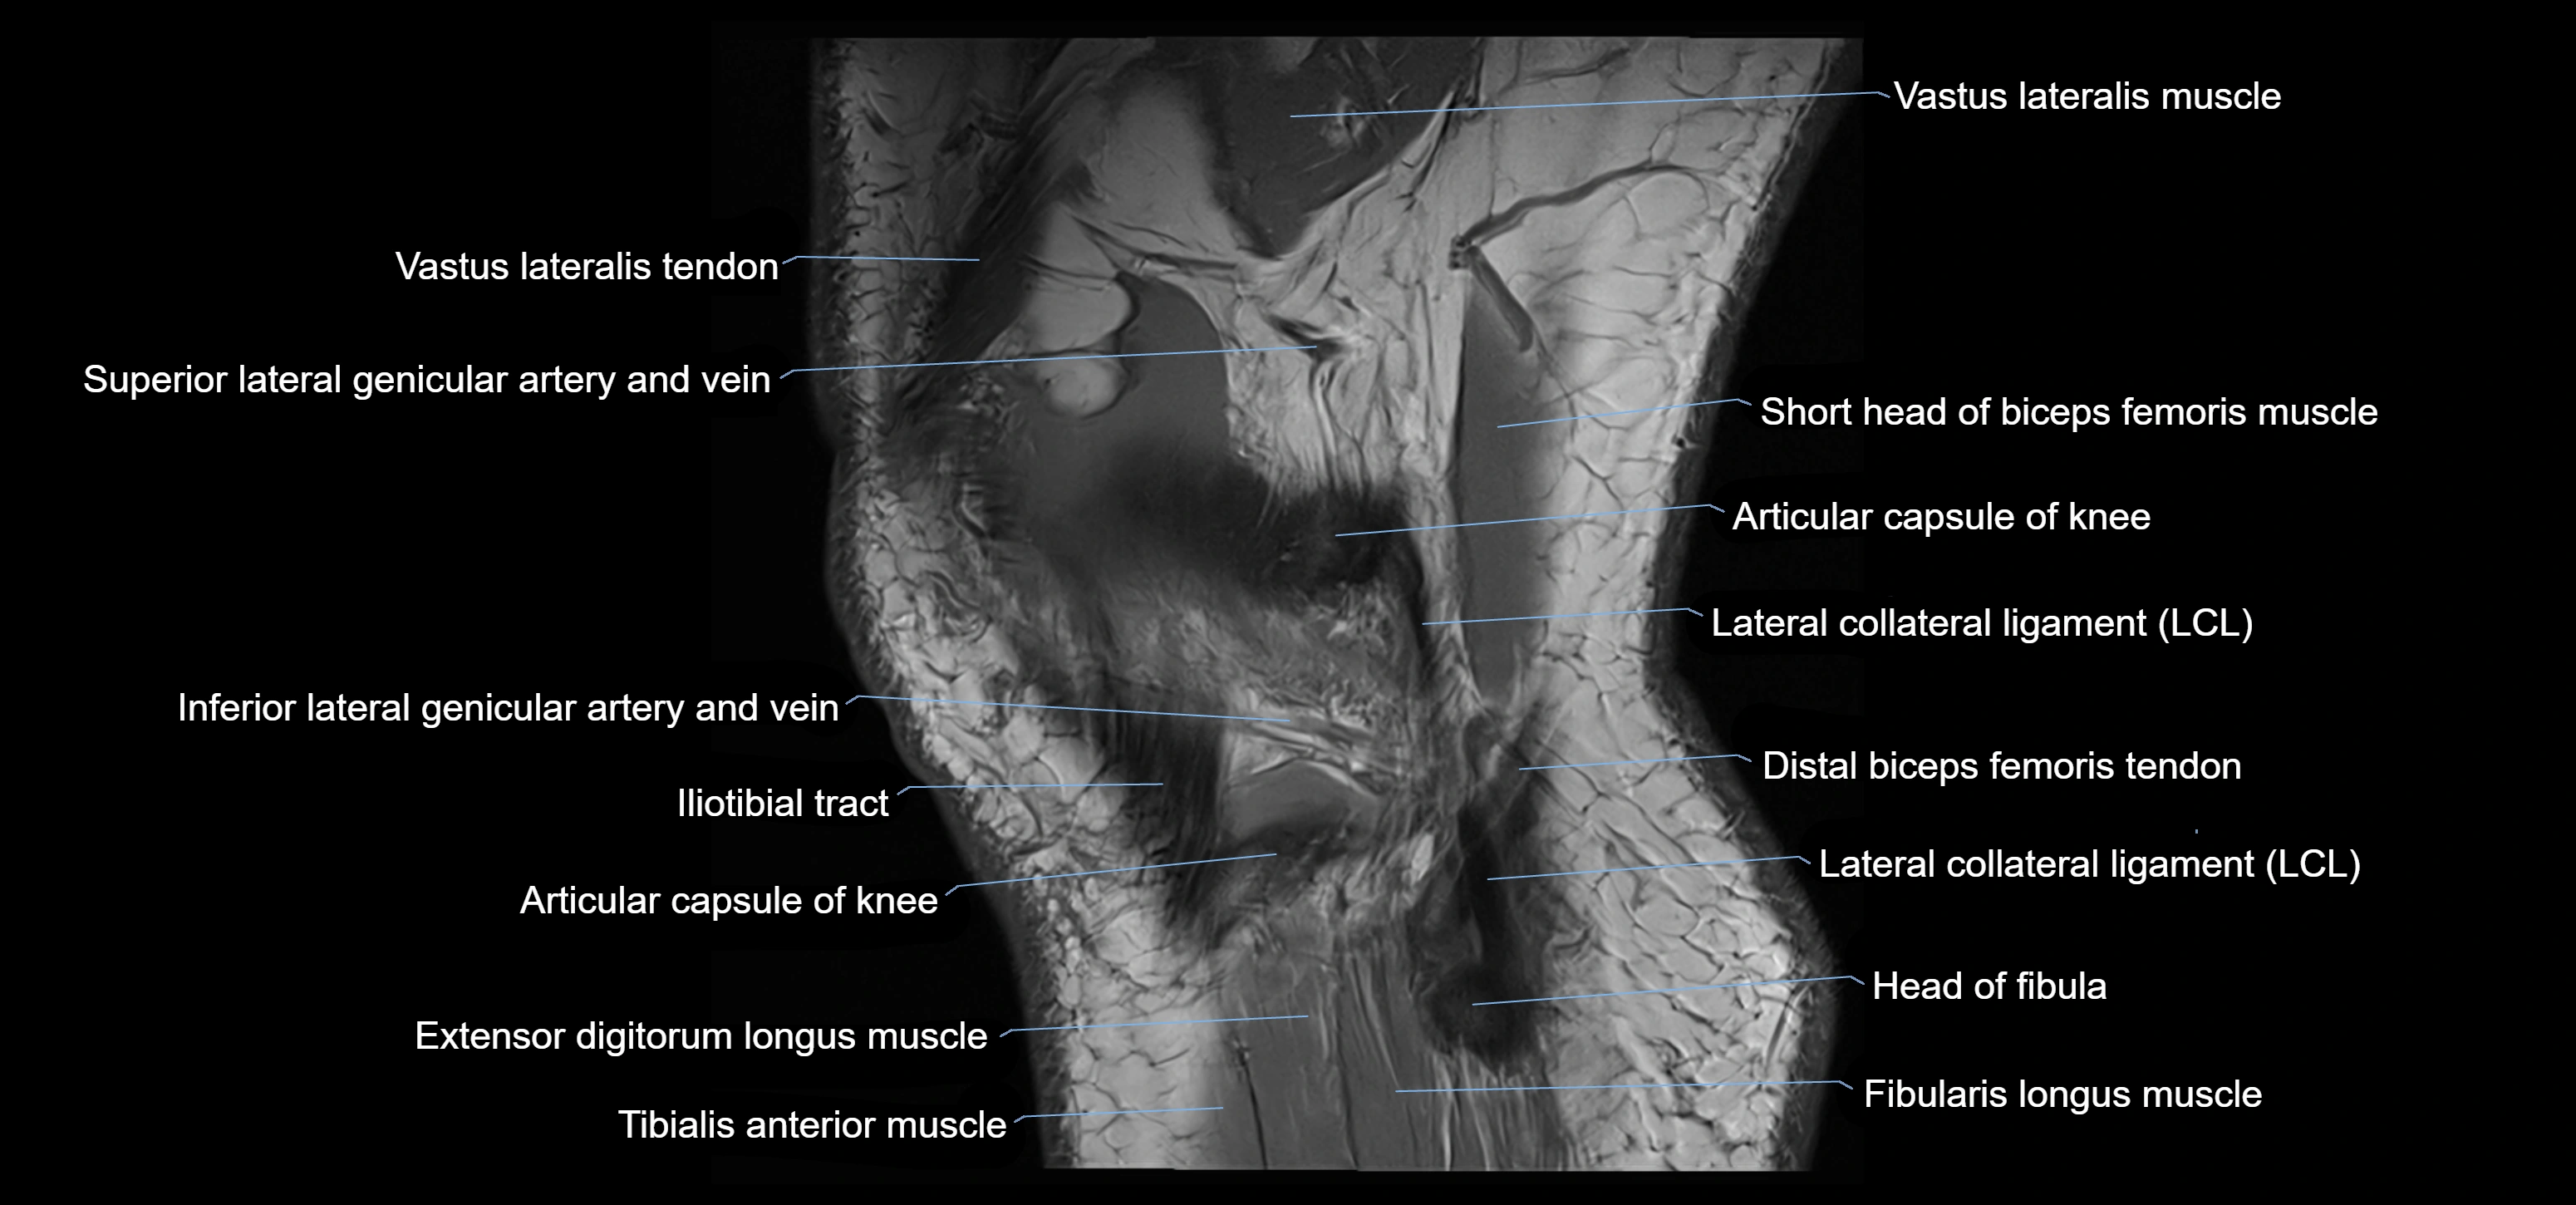

- Distal vastus lateralis tendon

- Extensor digitorum longus muscle

- Fibularis longus muscle (peroneus longus muscle)

- Head of fibula

- Inferior lateral genicular artery

- Inferior lateral genicular vein

- Lateral collateral ligament

- Lateral head of gastrocnemius muscle

- Superior lateral genicular artery

- Superior lateral genicular vein

- Tibialis anterior muscle

- Vastus lateralis muscle